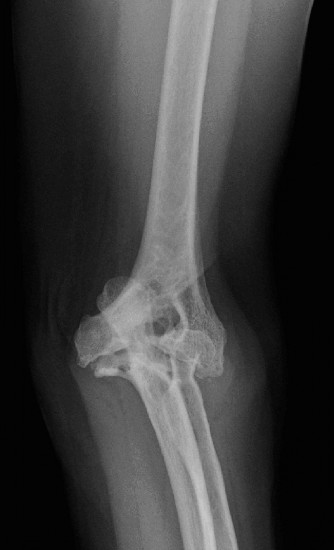

The patient undergoes resection arthroplasty with antibiotic cement spacer and a 6-week course of IV antibiotics. He returns to clinic 4 months later with improved pain, CRP <3, however, on examination he has a positive belly press sign and increased external rotation compared with the contralateral shoulder. Imaging is shown in Figure 2–57.

Figure 2–57

The correct answer is (D). The patient has completed his course of antibiotics and his spacer and is now an appropriate candidate for explanation of the cement spacer with revision shoulder arthroplasty, therefore Choices A and C are incorrect. The patient’s clinical examination findings point to rotator cuff tear (specifically subscapularis) which has occurred in the interval between his obtaining his initial total shoulder arthroplasty and his current examination. Therefore, total shoulder arthroplasty (Choice B) is contraindicated, and the patient should have a reverse total shoulder arthroplasty. Objectives: Did you learn...? Recognize the clinical presentation of a patient with infection after total shoulder arthroplasty?